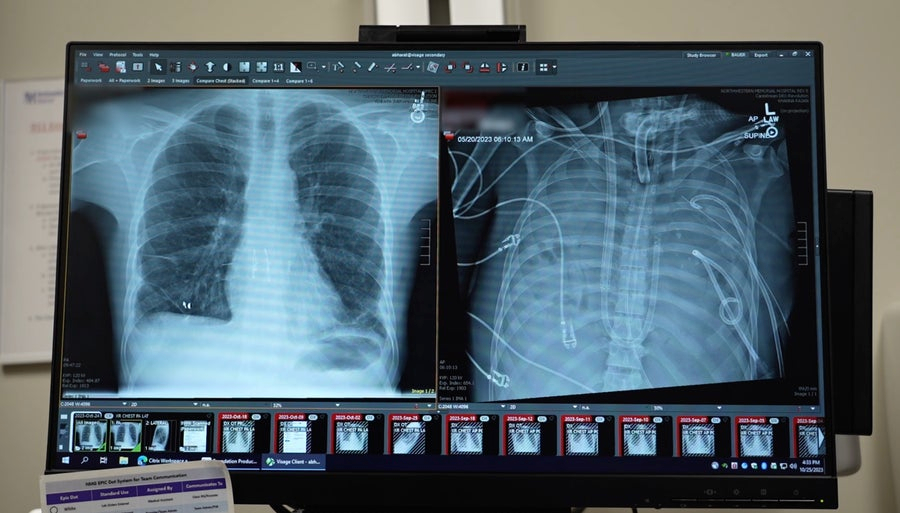

У 2023 році торакальний хірург Анкіт Бхарат працював у лікарні Northwestern Memorial Hospital, коли його залучили до лікування 33-річного пацієнта з грипом, який перебував на межі смерті. За словами лікаря, у чоловіка розвинулася вторинна інфекція, спричинена одним із найбільш небезпечних внутрішньолікарняних збудників, Pseudomonas, у зв’язку з чим його було підключено до апарата штучної вентиляції легень. Легені пацієнта заповнювалися рідиною та гноєм, функція нирок стрімко погіршувалася, а серце, за оцінкою лікаря, працювало лише мінімально. Стан пацієнта розцінювався як критичний і безпосередньо загрозливий для життя.

Згодом у пацієнта зупинилося серце. Реанімаційні заходи дозволили відновити серцеву діяльність, однак стало очевидно, що необхідні негайні та радикальні дії. Єдиним шансом на порятунок була двостороння трансплантація легень, проте стан хворого був настільки важким, що проведення такої операції на той момент вважалося неможливим. Водночас відсутність функціонуючих легень означала неминучу загибель пацієнта.

До цього моменту чоловік уже перебував на системі екстракорпоральної мембранної оксигенації, або ECMO, яка використовується для підтримки дихання і кровообігу. Проте, як пояснює лікар, така система не може ефективно працювати без наявності легень у тілі пацієнта. У відповідь на цю ситуацію команда розробила нестандартний підхід, який передбачав створення так званих штучних легень. Ця система мала забезпечити перекачування крові з правої половини серця до лівої, насичення її киснем та подальше транспортування до інших органів і тканин.

Принцип роботи нового рішення було порівняно з будівництвом мосту на автомагістралі. У нормальних умовах кров рухається з правої частини серця до легень, далі до лівої частини серця і потім розподіляється по всьому організму. За відсутності легень цей шлях обривається. Створена система фактично заповнила цю прогалину, забезпечуючи рух і оксигенацію крові замість легень. Для запобігання перевантаженню цієї умовної «транспортної ділянки» команда також розробила додатковий шлях, який дозволяв частині крові повертатися назад до правої частини серця.